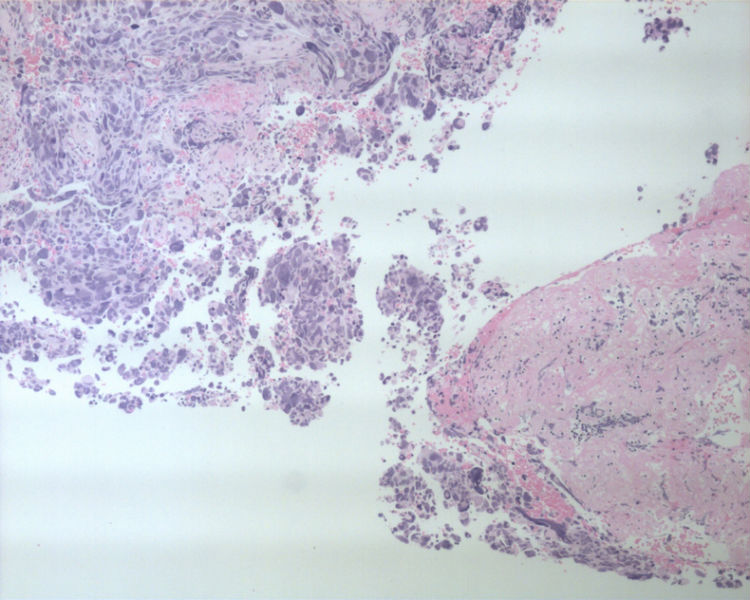

男性,50岁,右锁骨上淋巴结穿刺。

• 男性,50岁,右锁骨上淋巴结穿刺。图2

这是一例我以前穿刺的病例。当时涂片发现淋巴细胞的背景中散在大而非常异形的细胞。细胞没有成巢现象。

还好我当时在制作涂片的同时做了细胞腊块。现将细胞腊块的照片上传。

• 图1

• 图2

• 图3